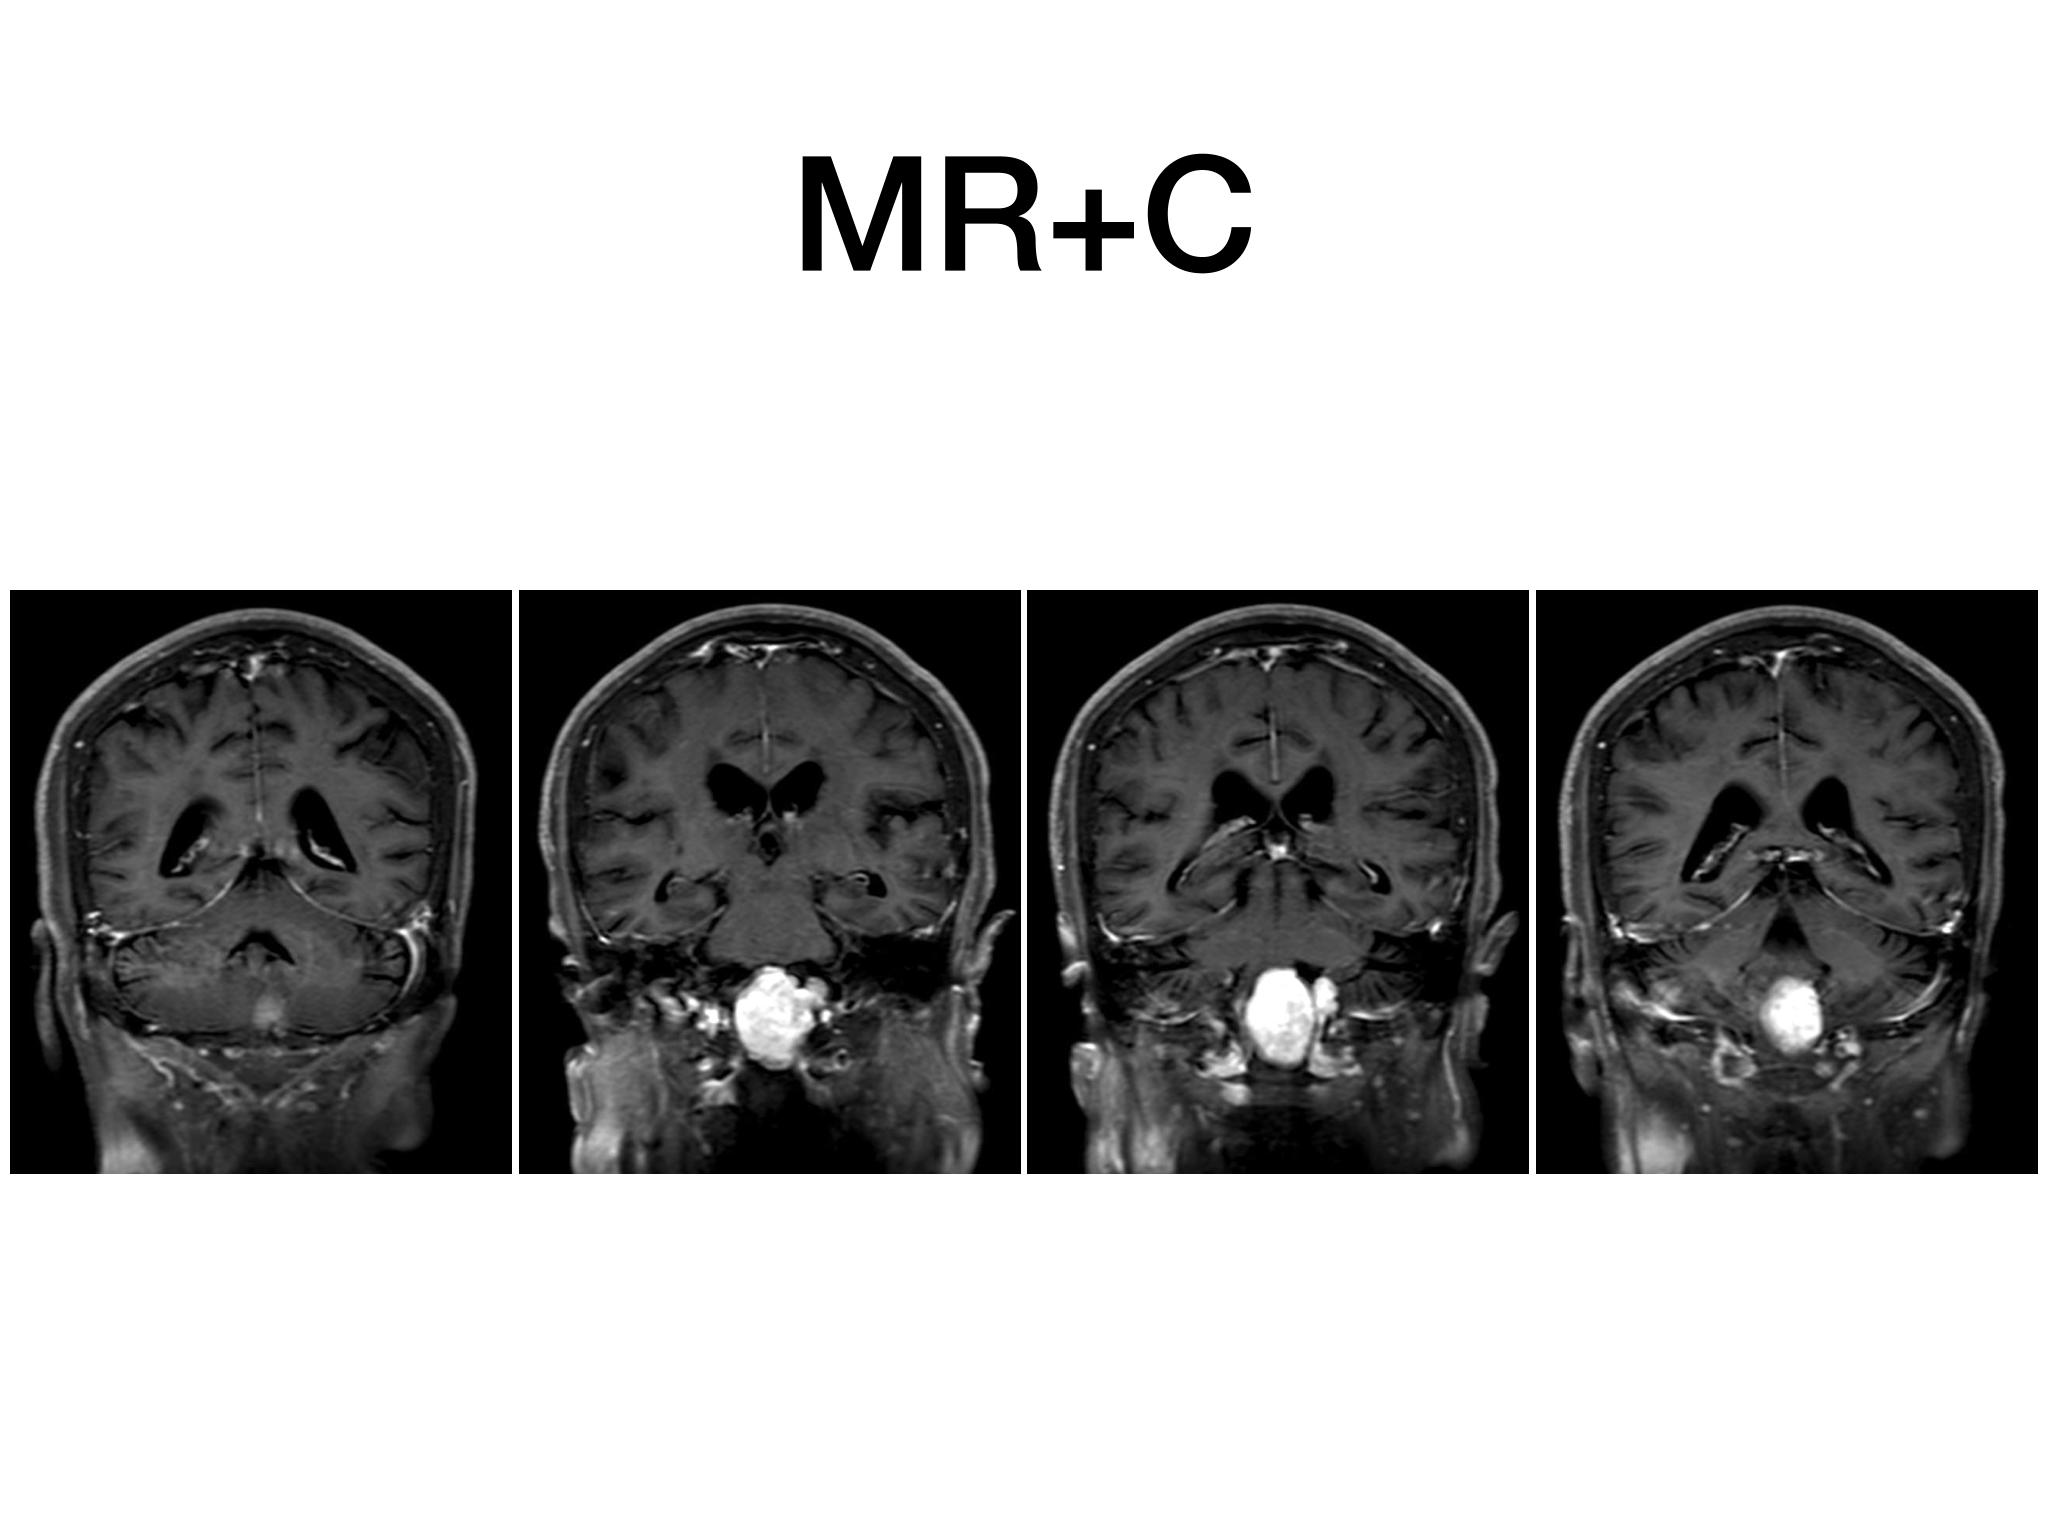

汇报一例后颅底肿瘤手术。为枕骨大孔巨大腹侧型脑膜瘤,该患者高龄,同时合并肺Ca,术前2周急性加重,枕骨大孔疝前期表现,术前已有延髓压迫及后组颅神经麻痹表现。经详细评估后采用远外侧经髁窝入路,最大化显露,重点保护延髓、后组颅神经,尽可能“零骚扰”。术中肿瘤质地韧,血供一般,与肿瘤上极与后组颅神经黏连紧密,最终99%切除,残留约1%,术后顺利康复出院,无新发症状,为后续进行肺部病变化疗创造有利条件。

远外侧经髁窝入路切除大型枕骨大孔腹侧脑膜瘤